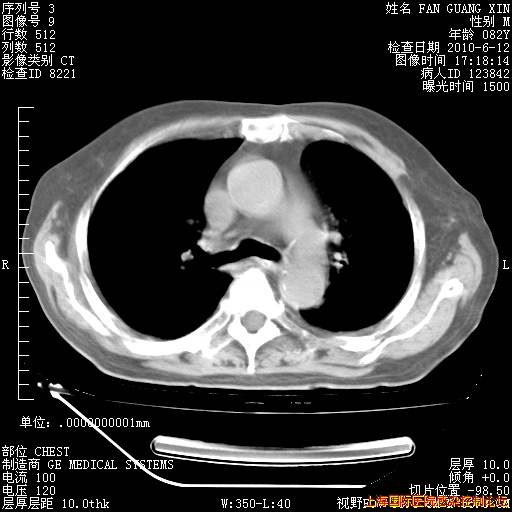

6月12日纵膈窗